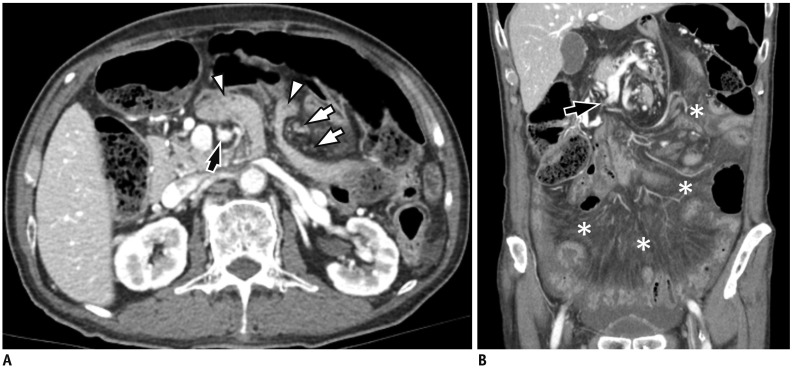

Fig. 14. Afferent loop syndrome due to adhesive ileus after subtotal distal gastrectomy with Billroth II reconstruction.

56-year-old male patient underwent subtotal gastrectomy with Billroth II reconstruction for early gastric cancer 2 years ago. He presented with abdominal pain and nausea.

A, B. On axial CT images, afferent limb (*) is markedly dilated with fluid, while efferent limb is not. B. Transition zone (arrow) is noted immediately distal to Treitz ligament in left abdomen. It shows beak-like appearance suggesting adhesive ileus. S = remnant stomach

Fig. 15. Internal hernia after total gastrectomy.

A. Axial CT image obtained at postoperative 1-year shows protrusion of small bowel (arrowheads) into anterior abdominal cavity passing between superior mesenteric artery (black arrow) and distal mesenteric arterial branches (white arrows), so-called mushroom sign. B. On coronal CT image, decreased caliber of superior mesenteric vein with beaked appearance (arrow), and extensive mesenteric congestion (*) are also seen. Laparotomy reveals Petersen's hernia.